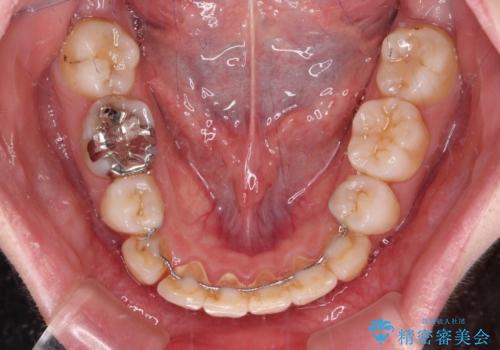

また、上顎臼歯は虫歯により抜歯されてから放置されている状態でした。

舌のトレーニングをしっかりと行っていただきながらワイヤー装置により矯正治療を行い、途中でインプラントを埋入し、矯正治療後に補綴治療を行うこととしました。